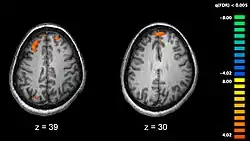

Schizofrenie je spojována s nepatrnými změnami ve struktuře mozku, zjištěnými u 40 až 50 % případů; a v chemických reakcích mozku během akutních psychotických stavů.[5] Studie využívající neuropsychologické testy a technologie zobrazování mozku (například fMRI a PET) ke zkoumání funkčních rozdílů v činnosti mozku ukázaly, že tyto rozdíly jsou nejčastěji patrné v čelních lalocích, hipokampu a spánkových lalocích.[60] V oblastech mozkové kůry čelního laloku a spánkových laloků bylo zjištěno zmenšení objemu mozku, i když v menší míře než u Alzheimerovy choroby. Není jasné, zda jsou tyto změny objemu postupné, nebo existují už před nástupem onemocnění.[61] Tyto rozdíly mají spojitost s neurokognitivním deficitem, často souvisejícím právě se schizofrenií.[62] Jelikož dochází ke změnám nervových okruhů, objevil se alternativní návrh, který chápe schizofrenii jako soubor neurovývojových poruch.[63]